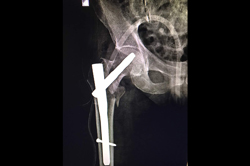

Subtrochanteric Fracture